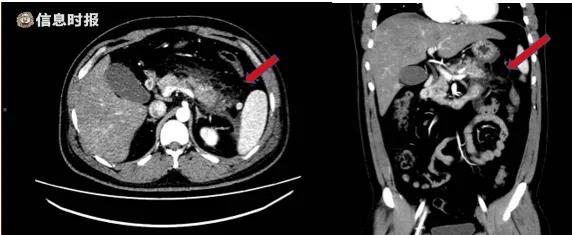

检验科的医师通过机器质检,结合腹部CT,确定小于得了急性坏死性胰腺炎和2型糖尿病伴酮症酸中毒。

腹部增强CT提示胰腺尾部肿胀,胰腺周围脂肪间隙模糊,多发斑片状、条索影。红色箭头示胰腺脂肪间隙。